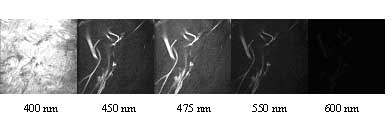

Figure

1. Representative spectral data and emission spectra for dermal layer

in human skin. |

We

have combined both two-photon imaging with spectroscopy in order

to extract information about the chemical components contributing

to the autofluorescence that we see in tissue. The analysis of tissue

spectroscopic information with 3-D microscopic resolution has major

advantages compared with typical tissue spectroscopy methods. Using

different analysis techniques such as multivariate curve resolution,

we are able to extract both the excitation and emission spectrum

of the different components, such as collagen, elastin, NADH, melanin,

and tryptophan. In addition, we are able to obtain the bulk emission

spectrum and examine the spectrum from different layers and individual

structures within the tissue.